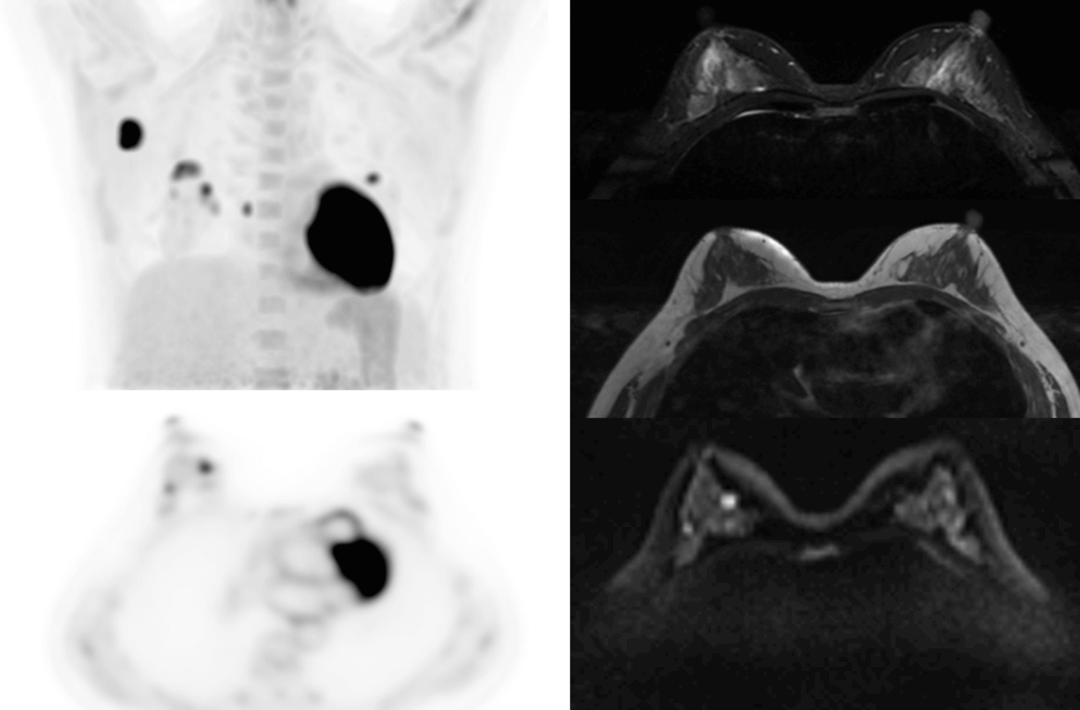

Compared with the conventional PET system with AFOV ranging between 20cm and 25cm, the 32cm long AFOV not only improves the sensitivity of the system, but also basically covers main organs of the whole body and the regional lymphatic system where metastasis may occur, and makes it possible to realize cancer TN staging in one bed position.

Traditionally, a PET/MR scan of a tumor patient takes about 35 to 50 minutes. The long AFOV can further optimize the PET/MR tumor scanning scheme. In other words, it can optimize the decision about whether to scan the whole body based on whether the tumor patient has regional lymphatic metastasis after regional PET/MR scan, potentially saving scan time for patients without metastasis.

In August 2019, Peking Cancer Hospital introduced United Imaging Healthcare's integrated PET/MR to make an in-depth exploration and optimization of cancer TNM staging under long AFOV. More than 500 examples of scanning various organs proved that long AFOV PET/MR could greatly increase the scan range over one bed position and improve the efficiency of cancer TNM staging.

The following are the cases of optimized TNM staging of breast cancer, esophageal cancer, prostate cancer and other diseases under the long axial field of "spatio-temporal integration" ULTRA-clear TOF PET/MR.  Thanks to Capital Medical University Xuanwu Medical Treatment for providing the image.